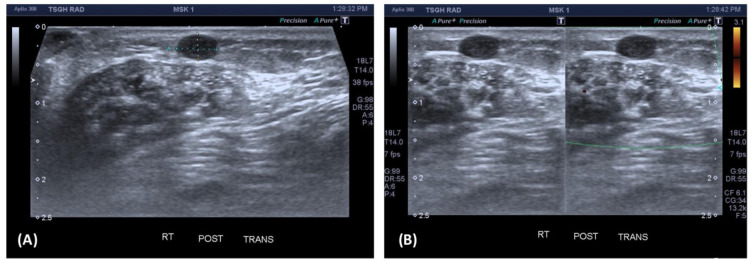

Case report: We report the case of a 51-year-old female with a six-month history of a painful, palpable mass in the right heel. Physical examination revealed a soft, mobile, and tender subcutaneous nodule. Ultrasound imaging identified a 0.5 cm well-defined hypoechoic lesion in the subcutaneous layer, without internal blood flow, initially suspected to be an epidermoid cyst or fibrous tumor. Surgical excision of the lesion was performed, and histopathological analysis revealed a well-encapsulated tumor consisting of spindle-shaped cells with eosinophilic cytoplasm and bland nuclei, accompanied by vascular components. Immunohistochemical staining confirmed positive expression of SMA, establishing the diagnosis of angiomyoma. The patient experienced an uneventful postoperative recovery.